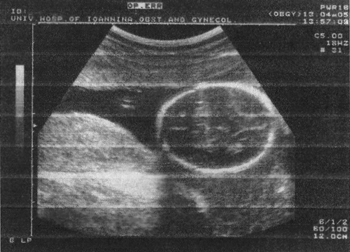

AC (εικόνα 3)

Είναι η λιγότερο αξιόπιστη μέθοδος. Χρησιμοποιείται κυρίως στη διαφορική διάγνωση της ενδομήτριας καθυστέρησης ανάπτυξης (IUGR), ή στη διάγνωση των διαφόρων ανάπτυξης μεταξύ διδύμων.(14,17)

Εικόνα 3. AC. Περίμετρος κοιλίας εμβρύου. Εικόνα 4. FDL. Μήκος διαφύσεως μηριαίου οστού. Εκτίμηση ηλικίας κύησης 2ου και 3ου τριμήνου.

FDL (εικόνα 4)

Προκύπτουν διαφορές σε όλη τη διάρκεια της κυήσεως, μέχρι και 2.8 εβδομάδων. Έχει την ίδια αξιοπιστία με την BPD στο 2ο τρίμηνο της κυήσεως. Μελέτες έχουν δείξει μεγαλύτερη αξιοπιστία στο 3ο τρίμηνο, σε σχέση με την BPD.(17-19)